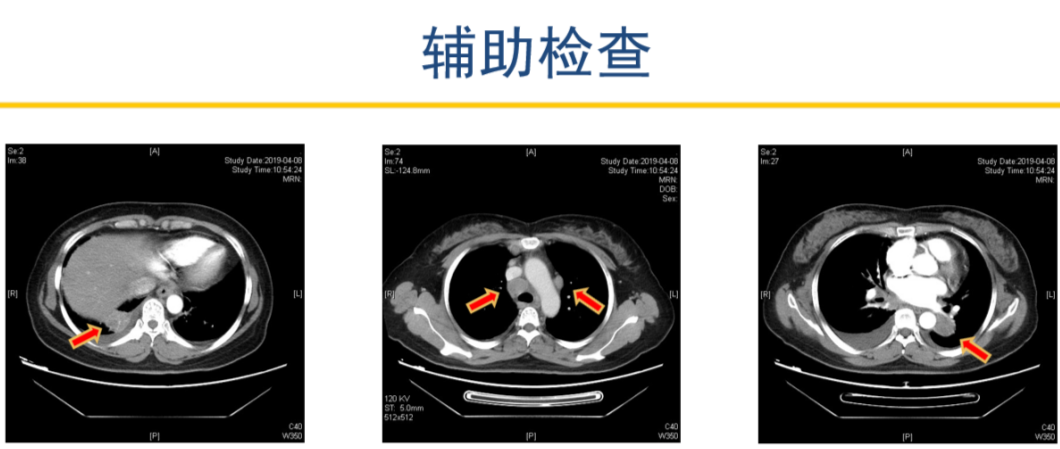

患者2019-04-08 胸部增强CT,显示左肺下叶占位并纵隔、双肺门、右锁骨上多发肿大淋巴结,考虑肺癌可能。右下肺占位,建议抗炎治疗后复查。

2019-04-12 PET-CT显示①右肺下叶后基底段胸膜下软组织密度肿块(大小26*30mm)。

②左肺下叶纵隔旁软组织密度肿块(大小28*31mm)。

③双肺门、纵隔内隆突下、气管旁、主肺动脉窗、血管前间隙、右侧颈部Ⅴ区及锁骨区多发增大淋巴结。

至此为止,患者的诊断为:肺恶性肿瘤 小细胞癌 广泛期 cT4N3M0 IIIC期(病灶1:右肺下叶,病灶2:左肺下叶),此时先给予标准化疗方案,EP方案:依托泊苷100mg/㎡  d1-3+顺铂75mg/㎡ d1-2 q21d*2。结果如下: